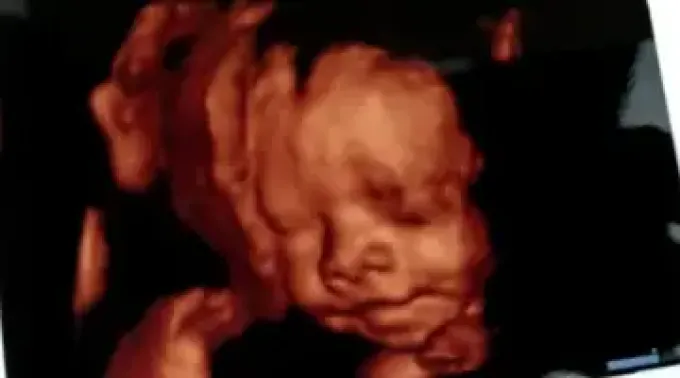

No dia 3 de outubro, por ocasião da marcha “A favor das mulheres e da vida”, que reuniu 300 mil pessoas na Cidade do México e cerca de um milhão em todo o país, um médico realizou uma ultrassonografia em Ana, uma adolescente de 15 anos com 38 semanas de gestação.

O vídeo de ultrassom desatou a ira dos promotores do aborto, que fizeram vários insultos e ameaças.

Ao mesmo tempo, o vídeo se tornou viral, atingindo cerca de 11 milhões de pessoas, com cerca de 2 milhões de visualizações.